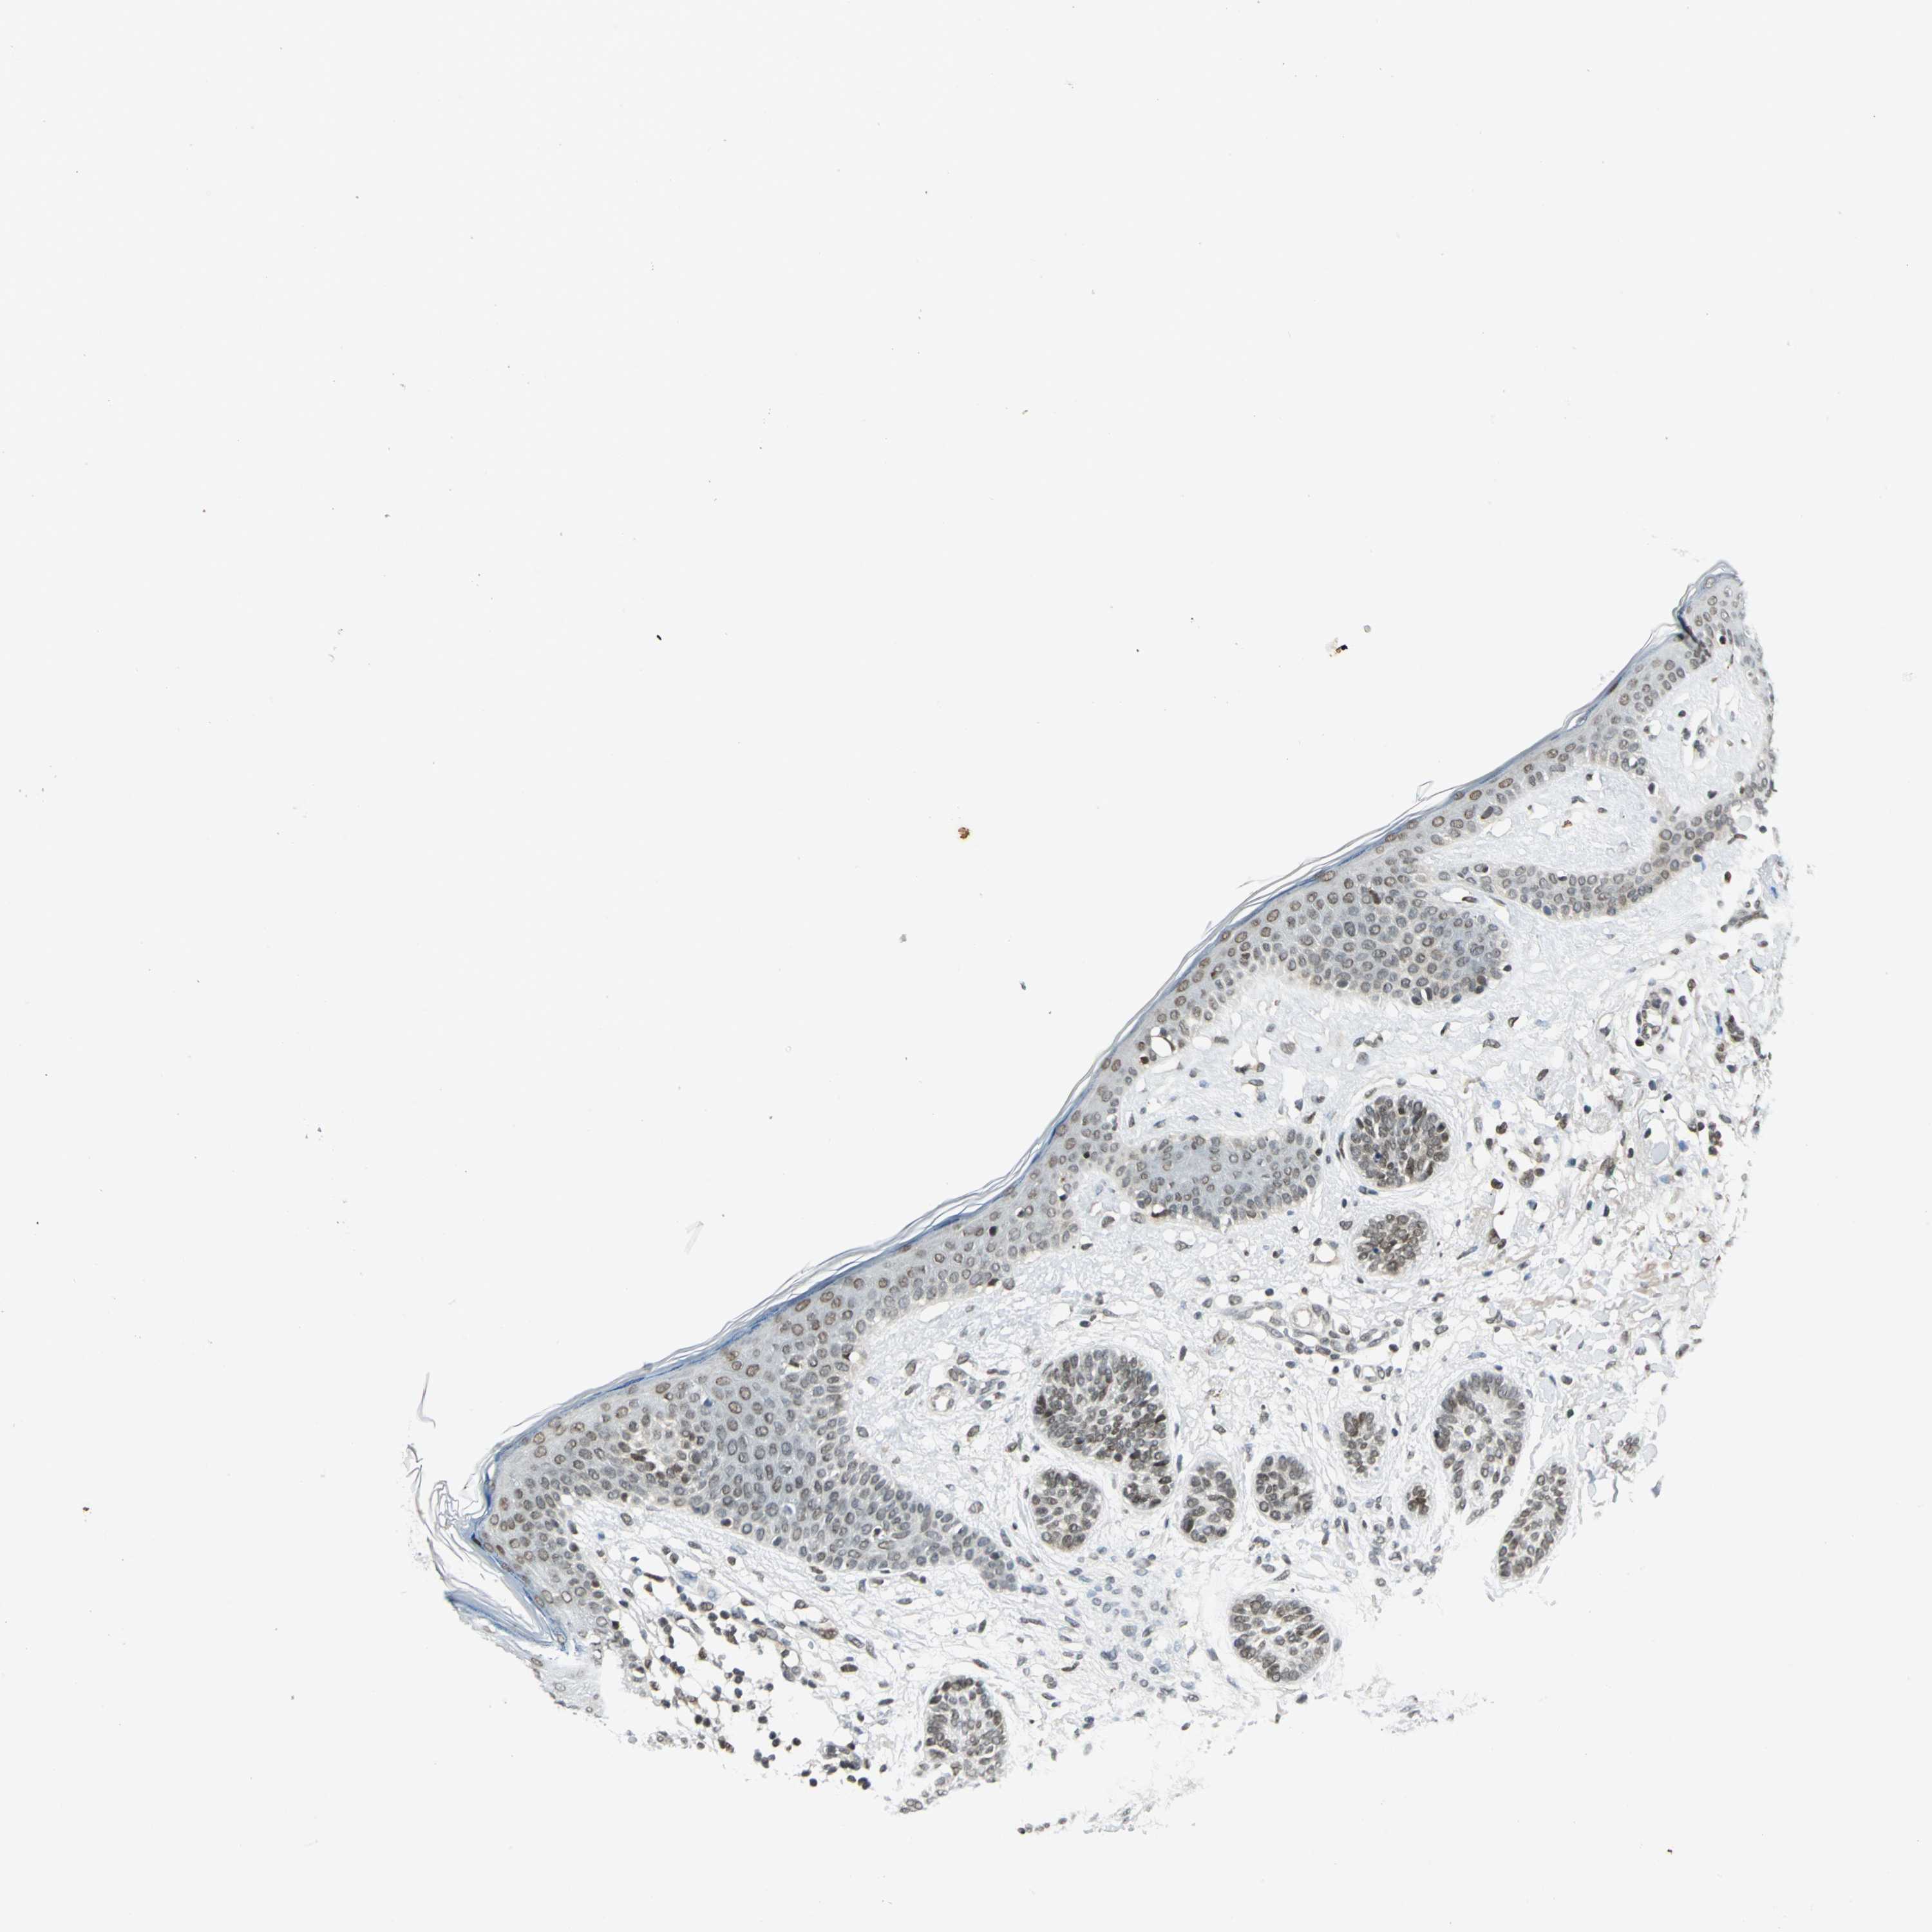

Basal cell and squamous cell cancer

SKIN CANCER - Protein expressioni

A mouse-over function shows sample information and annotation data. Click on an image to view it in a full screen mode. Samples can be filtered based on level of antibody staining by selecting one or several of the following categories: high, medium, low and not detected. The assay and annotation is described here.

Antibody stainingi

Antibody staining in the annotated cell types in the current human tissue is reported as not detected, low, medium, or high, based on conventional immunohistochemistry profiling in selected tissues. This score is based on the combination of the staining intensity and fraction of stained cells.

Each image is clickable and will lead to virtual microscopy that enables deeper exploration of all samples and also displays staining intensity scores, fraction scores and subcellular localization as well as patient and tissue information for each sample.

Antibody HPA005448

Staining

High

Intensity

Strong

Quantity

>75%

Location

Nuclear

Basal cell carcinoma